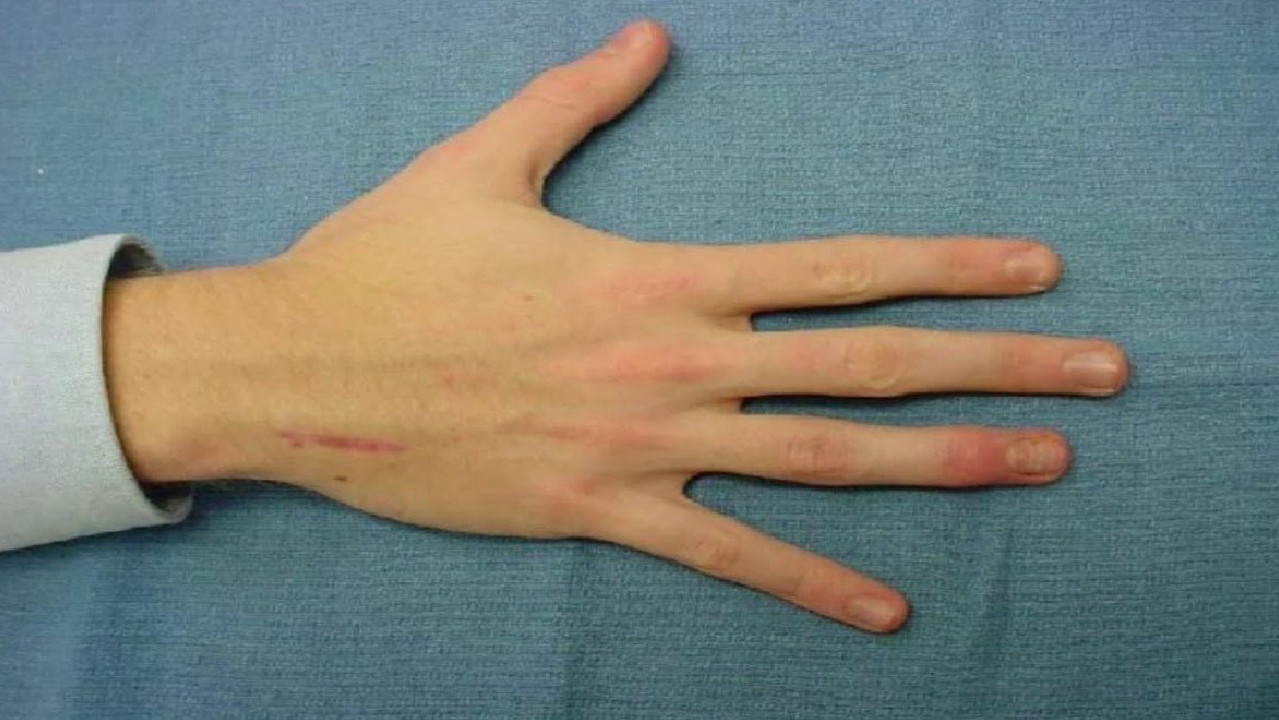

Sindrom marfana tema nauchnoj stati po klinicheskoj medicine chitajte besplatno tekst nauchno issledovatelskoj raboty v elektronnoj biblioteke kiberleninka (Тип файлу jpg)

Sindrom Marfana Tema Nauchnoj Stati Po Klinicheskoj Medicine Chitajte Besplatno Tekst Nauchno Issledovatelskoj Raboty V Elektronnoj Biblioteke Kiberleninka

Neonatalnaya forma sindroma marfana klinicheskoe opisanie i kompleksnyj podhod k diagnostike i lecheniyu tema nauchnoj stati po klinicheskoj medicine chitajte besplatno tekst nauchno issledovatelskoj raboty v elektronnoj biblioteke kiberleninka (Тип файлу jpg)

Neonatalnaya Forma Sindroma Marfana Klinicheskoe Opisanie I Kompleksnyj Podhod K Diagnostike I Lecheniyu Tema Nauchnoj Stati Po Klinicheskoj Medicine Chitajte Besplatno Tekst Nauchno Issledovatelskoj Raboty V Elektronnoj Biblioteke Kiberleninka

Neonatalnaya forma sindroma marfana klinicheskoe opisanie i kompleksnyj podhod k diagnostike i lecheniyu tema nauchnoj stati po klinicheskoj medicine chitajte besplatno tekst nauchno issledovatelskoj raboty v elektronnoj biblioteke kiberleninka (Тип файлу jpg)

Neonatalnaya Forma Sindroma Marfana Klinicheskoe Opisanie I Kompleksnyj Podhod K Diagnostike I Lecheniyu Tema Nauchnoj Stati Po Klinicheskoj Medicine Chitajte Besplatno Tekst Nauchno Issledovatelskoj Raboty V Elektronnoj Biblioteke Kiberleninka

Sindrom marfana tema nauchnoj stati po klinicheskoj medicine chitajte besplatno tekst nauchno issledovatelskoj raboty v elektronnoj biblioteke kiberleninka (Тип файлу jpg)

Sindrom Marfana Tema Nauchnoj Stati Po Klinicheskoj Medicine Chitajte Besplatno Tekst Nauchno Issledovatelskoj Raboty V Elektronnoj Biblioteke Kiberleninka